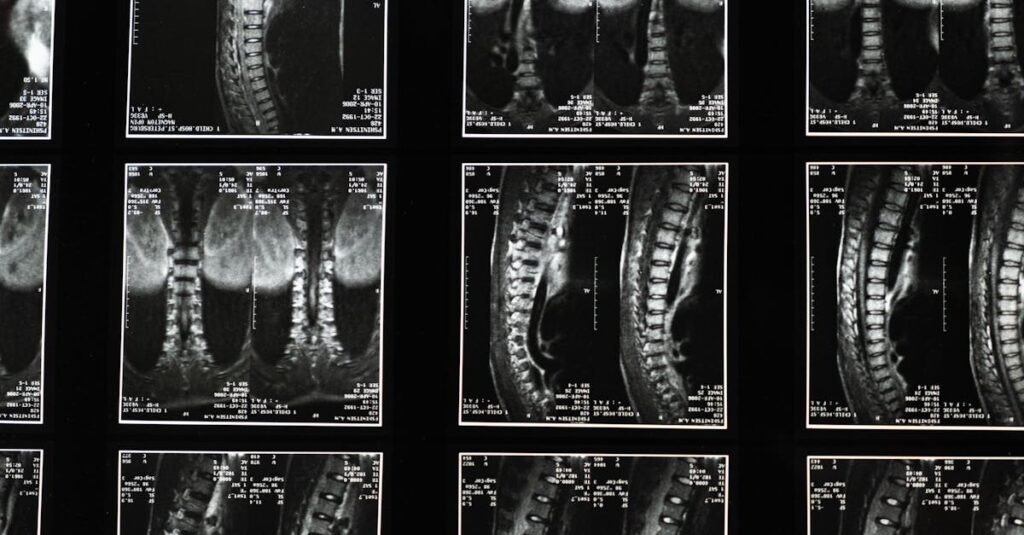

Ce podcast médical décrit les bombements et hernies discales, distinguant ces affections selon la gravité de la dégénérescence discale. Il détaille leurs causes, symptômes, diagnostics (souvent […]

La décompression spinale est une technique thérapeutique visant à soulager les douleurs liées aux affections de la colonne vertébrale. Elle s’adresse à ceux qui rencontrent des problèmes comme la hernie discale, le bombement discal ou la sténose spinale. En utilisant des méthodes non invasives, cette approche vise à réduire la pression sur les disques intervertébraux, favorisant ainsi la circulation sanguine et le processus de guérison dans la région du dos.

La décompression spinale est une méthode thérapeutique qui répond à des pathologies variées liées à la colonne vertébrale, notamment les troubles tels que les hernies discales, les bombements discaux et les sténoses spinales. Ces conditions peuvent entraîner des douleurs aiguës et chroniques, ainsi qu’une diminution de la qualité de vie. Grâce à une approche personnalisée, la décompression spinale s’adapte aux besoins spécifiques de chaque patient, vis-à-vis des douleurs qu’il ressent.